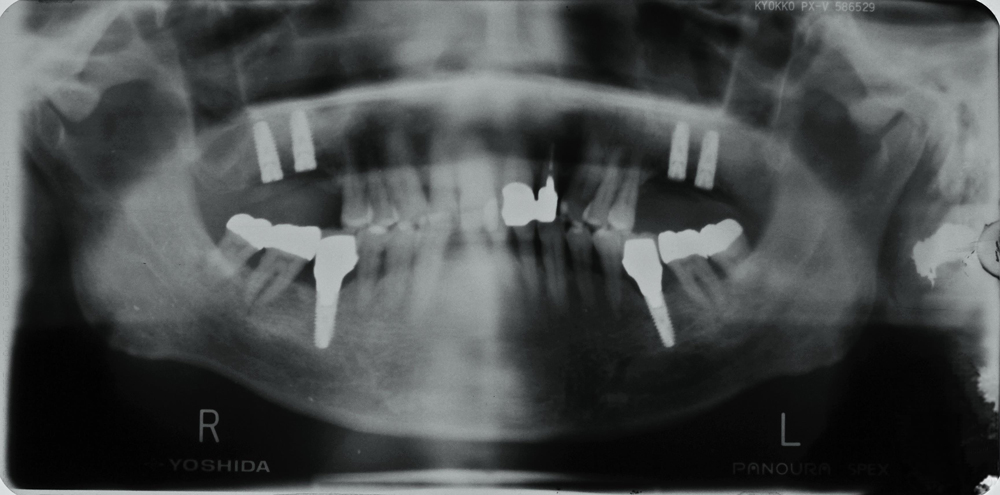

④重度の歯周病で多数の抜歯に至ったケース

【60歳 男性】

重度の歯周病のため多数の歯が抜歯となりました。

入れ歯は入れたくないという患者の要望にお応えすべく、残った歯に対する歯周病治療

+ 左右の上顎臼歯部に対する増骨手術 +

インプラント治療を実施しました。

治療の結果、入れ歯の装着は免れましたが、このような複雑なケースでは歯とインプラントの維持のために定期的なメンテナンスを行うことがより一層重要となります。

このケースでは、歯科治療終了後に内科的疾患のため唾液の分泌量が減少したことにより、むし歯が発生しやすい状況となり、改めてメンテナンスの重要性が痛感されました。